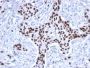

The specificity of this monoclonal antibody to its intended target was validated by HuProt™ Array, containing more than 19, 000, full-length human proteins. Recognizes a 53 kDa protein, which is identified as p53 suppressor gene product. It reacts with the mutant as well as the wild form of p53. It is a tumor suppressor protein expressed in a wide variety of tissue types and is involved in regulating cell growth, replication, and apoptosis. It binds to MDM2, SV40 T antigen and human papilloma virus E6 protein. Positive nuclear staining with p53 antibody has been reported to be a negative prognostic factor in breast, lung, colorectal, and urothelial carcinoma. Anti-p53 positivity has also been used to differentiate uterine serous carcinoma from endometrioid carcinoma as well as to detect intratubular germ cell neoplasia. Mutations involving p53 are found in many malignant tumors, including breast, ovarian, bladder, colon, lung, and melanoma.Primary antibodies are available purified, or with a selection of fluorescent CF® Dyes and other labels. CF® Dyes offer exceptional brightness and photostability. Note: Conjugates of blue fluorescent dyes like CF®405S and CF®405M are not recommended for detecting low abundance targets, because blue dyes have lower fluorescence and can give higher non-specific background than other dye colors.

MDA-MB-231 Cells. Breast or Colon carcinoma

IHC, FFPE (verified), WB (verified)

IHC (FFPE) (verified)|WB (verified)

Higher concentration may be required for direct detection using primary antibody conjugates than for indirect detection with secondary antibody|Immunohistology (formalin): 0.5-1.0 ug/mL for 30 minutes at RT|Staining of formalin-fixed tissues requires boiling tissue sections in 10 mM citrate buffer, pH 6.0, for 10-20 minutes followed by cooling at RT for 20 minutes|Optimal dilution for a specific application should be determined by user